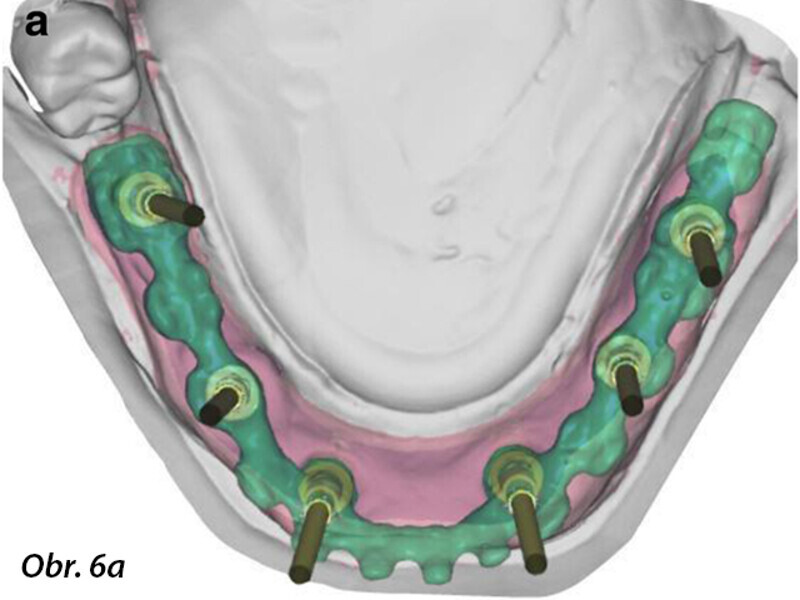

Počítačem asistované, šablonou se řídící okamžité zavedení a zatížení implantátu v dolní čelisti